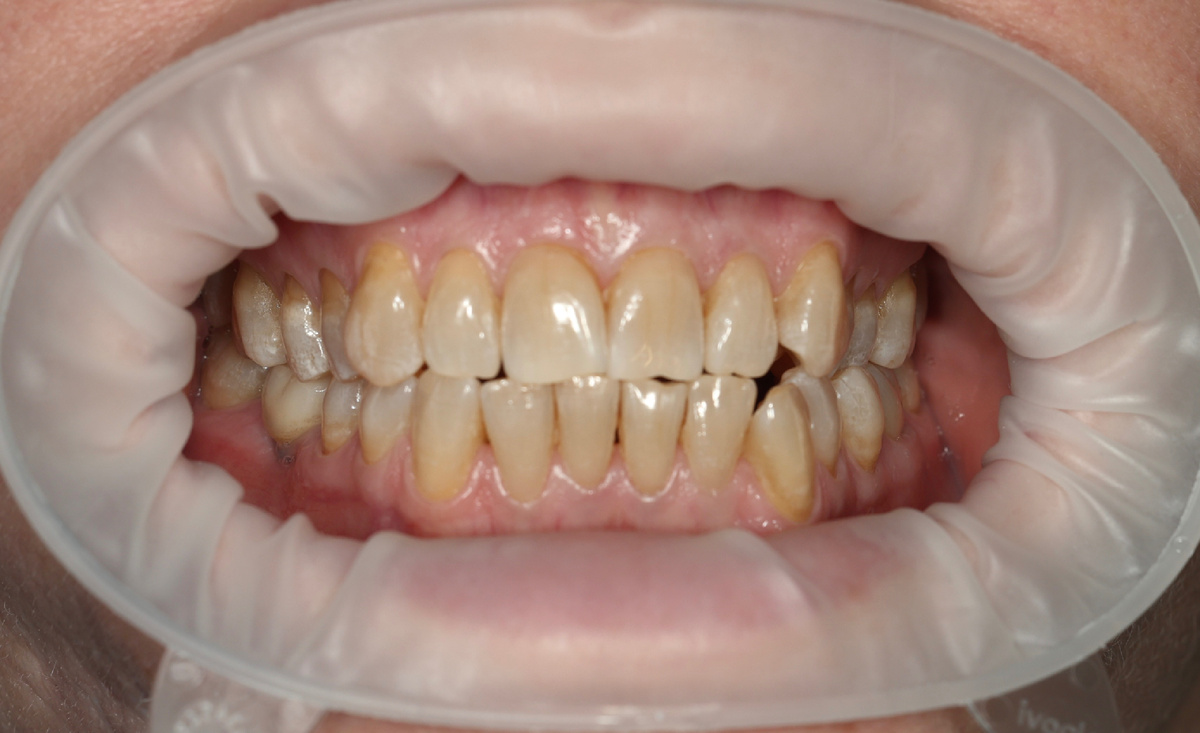

Затем рассматриваю ситуацию во рту - только комплексно можно оценить реальную картину и правильно интерпретировать состояние. Что вижу - признаков хронического воспаления тканей пародонта нет:

• дёсны бледно-розовые, плотные;

• кровоточивости нет;

• межзубные сосочки на месте;

• нет деструкции кости, костные перегородки сохранны, костные карманы не определяются.

Это не пародонтит. Это перегрузочный тип рецессий - невоспалительный. А прикус у пациентки весьма интересный.

Состояние до - невоспалительные рецессии